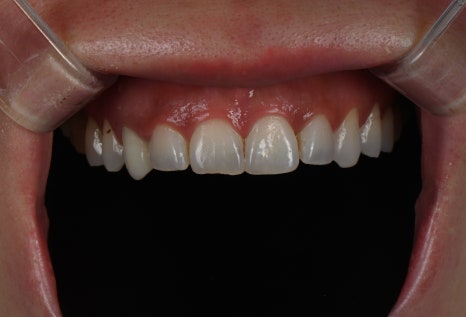

시술명 : 라미네이트

왼 : 시술 전 / 오 : 시술 후 5일 경과